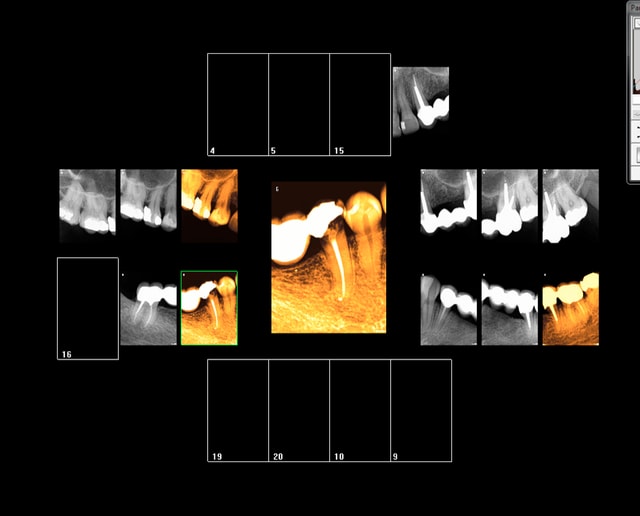

Rebelote aujourd'hui. Pulpite sur 15.

Re re belote. pulpite 38. -))))

Pas venu depuis 2007 date de la pose d'onlays sur 45 46.

On va pas refaire le débat, mais ou bien je suis un mutilator, ou bien je suis lobotomisé, mais il ne me semble pas aberrant de poser IC/Cr sur cette 15 non ?, je me vois pas y coller un onlay.

Après Chicot, on a les mêmes qui consultent quand ça picote sérieux, et en général l'indication du coiffage MTA,biodentine/inlay/onlay, n'est plus vraiment d'actualité.

En général c'est déjà limite pour la couronne alors ...

Suivant : 47 pétée en distal mais pas de douleur ( dernier RDV 2008) . Chiotte elle pouvait pas attendre un peu avant de péter ? j'aime bien les actes qui solvabilisent à la fois le patient et le praticien pas ces soins opposables à un tarif de merde. -)))

Ah ! enfin une endo au résultat non aléatoire sur 36 ! spéciale dédicace pour améli ! -))))

Suivant : 45 cassée ( jadis un onlay support de bridge ? ) Dent gardée vivante puis endo à travers l'onlay je suppose. ca marche moins bien après forcément. -))))

Maintenant la question que je me pose , vais je continuer à soigner les caries moyennes révélées ailleurs par les radios ? Vu qu'on nous prend pour des cons, hein ?

En plus faire les radios et les coter c'est prendre le risque de se faire emmerder par un CDC, autant ne plus en faire non ? ca résoud le problème de conscience que je pourrais me poser à l'avenir ! Il suffira d'attendre les signes d'appels et d'avoir des stocks de R25 ! -))))

Suivant : douleurs 36. Abcès du à un Syndrome du septum dent vivante, dommage.......-)))))

Dernier rendez vous chez le dentiste : 12 ans ( extractions des sagesses)

Notez l'indication des rétro coronaires et de la rétro alvéolaire dans ce cas : pas d'antécédents de soins intensifs et atteinte pulpaire suspectée ( élimination d'un 4ième degré, fais le test au froid après) . -)))))